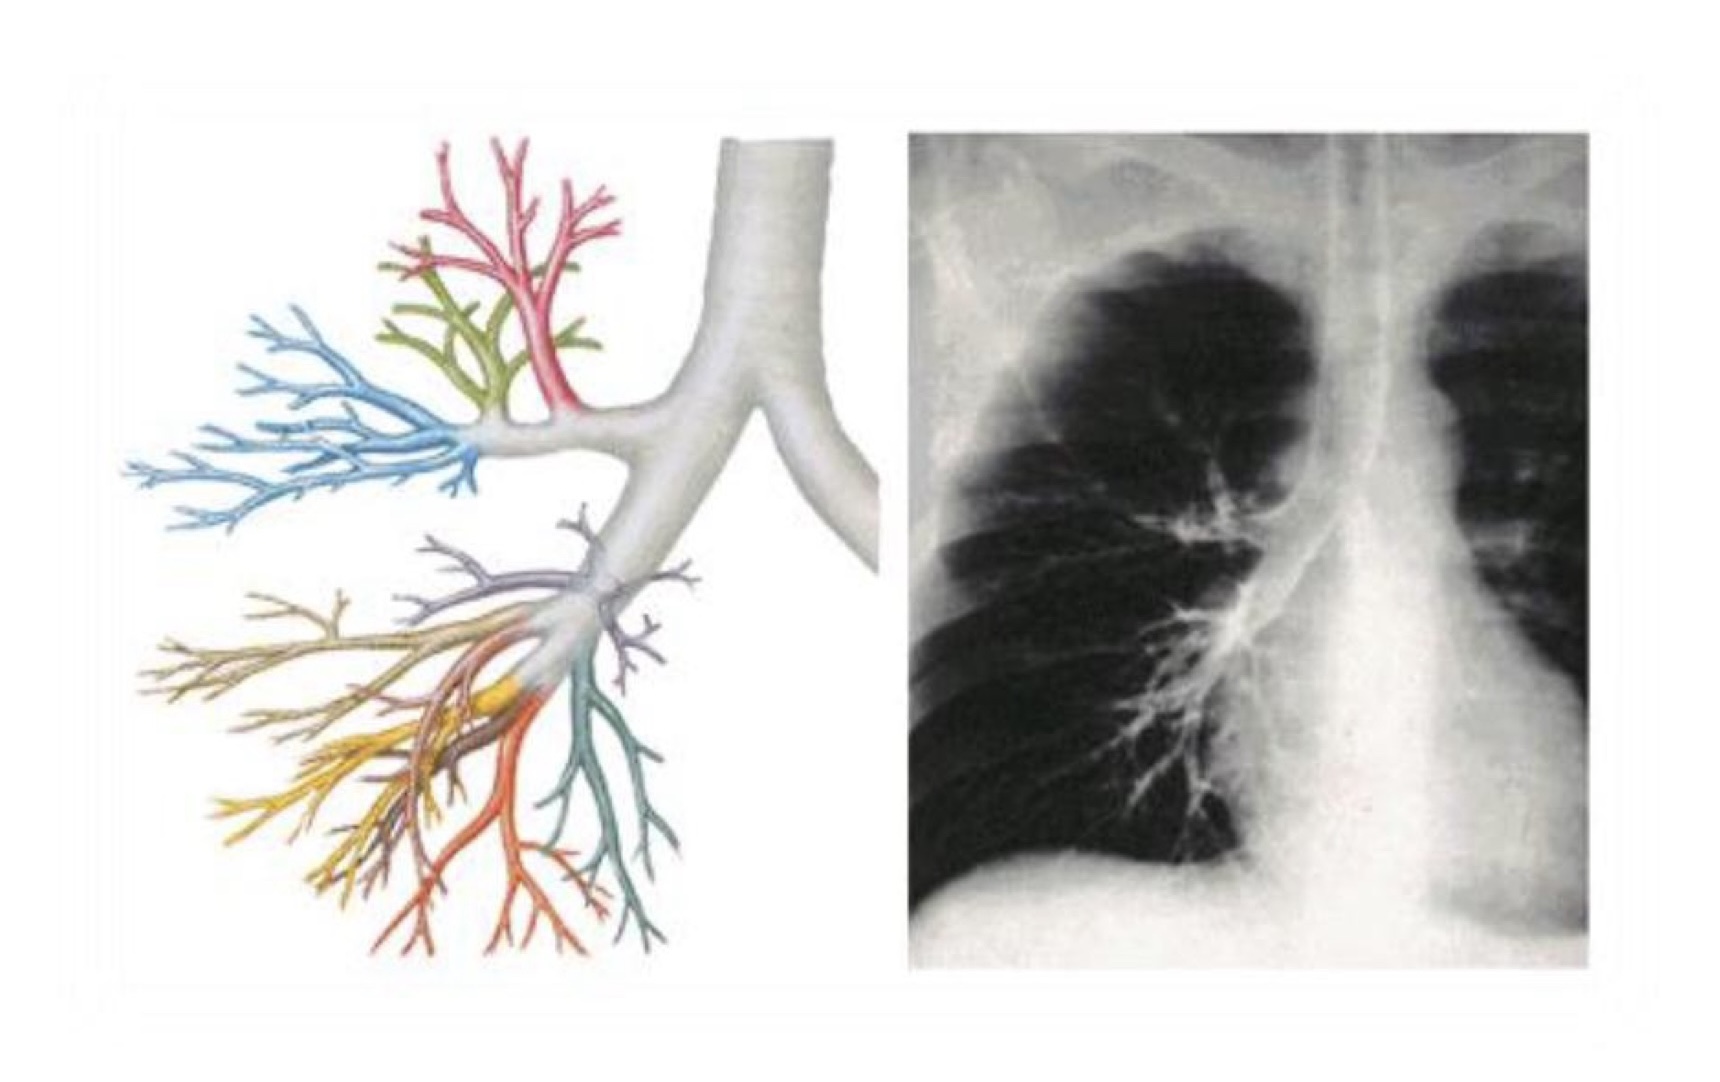

Các phân thuỷ phế quản phổi

Cây phế quản

Khuynh hướng dị vật vào khí quản sẽ dễ đi vào phế quản chính phải hơn so với PQ chính trải vì phế quản phải chếch góc ít hơn, to hơn, ngắn hơn và nếu nằm ngửa thì dễ đi vào S6 phải nhất